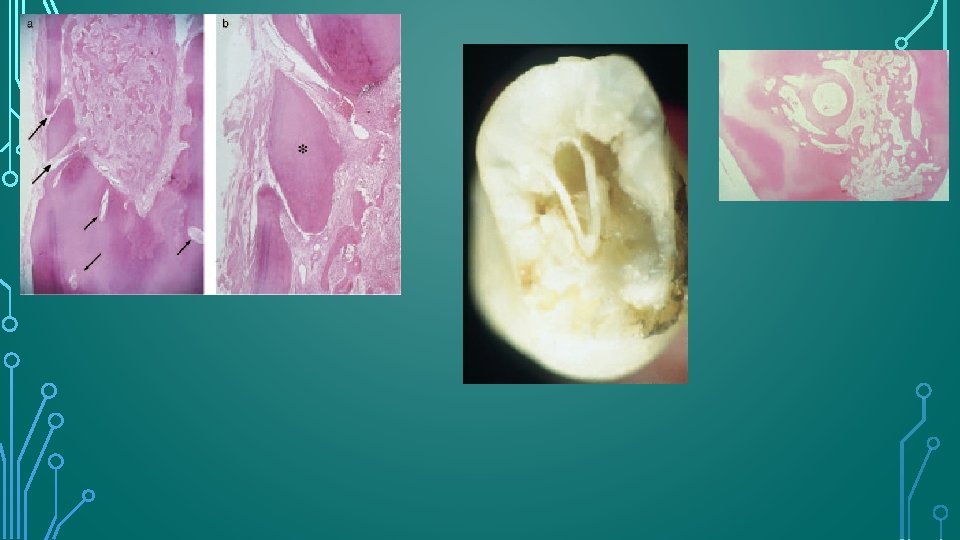

HISTOLOGIC APPEARANCE • Same as that of other forms of resorption , with certain unique feature reflecting the invasive nature of the process. • Narrow “channels” of resorption extend through the dentin and may communicate with the periodontal ligament.

HISTOLOGIC APPEARANCE • Pulpal tissue was populated to varying degrees in all teeth with an inflammatory infiltrate composed predominantly of lymphocytes and macrophages. • The odontoblast layer and predentin were absent from the affected dentinal walls, which were populated by large, multinucleated odontoclasts occupying resorption lacunae. • Islands of mineralized tissue occupying the root canal space are the defining feature of internal replacement resorption.